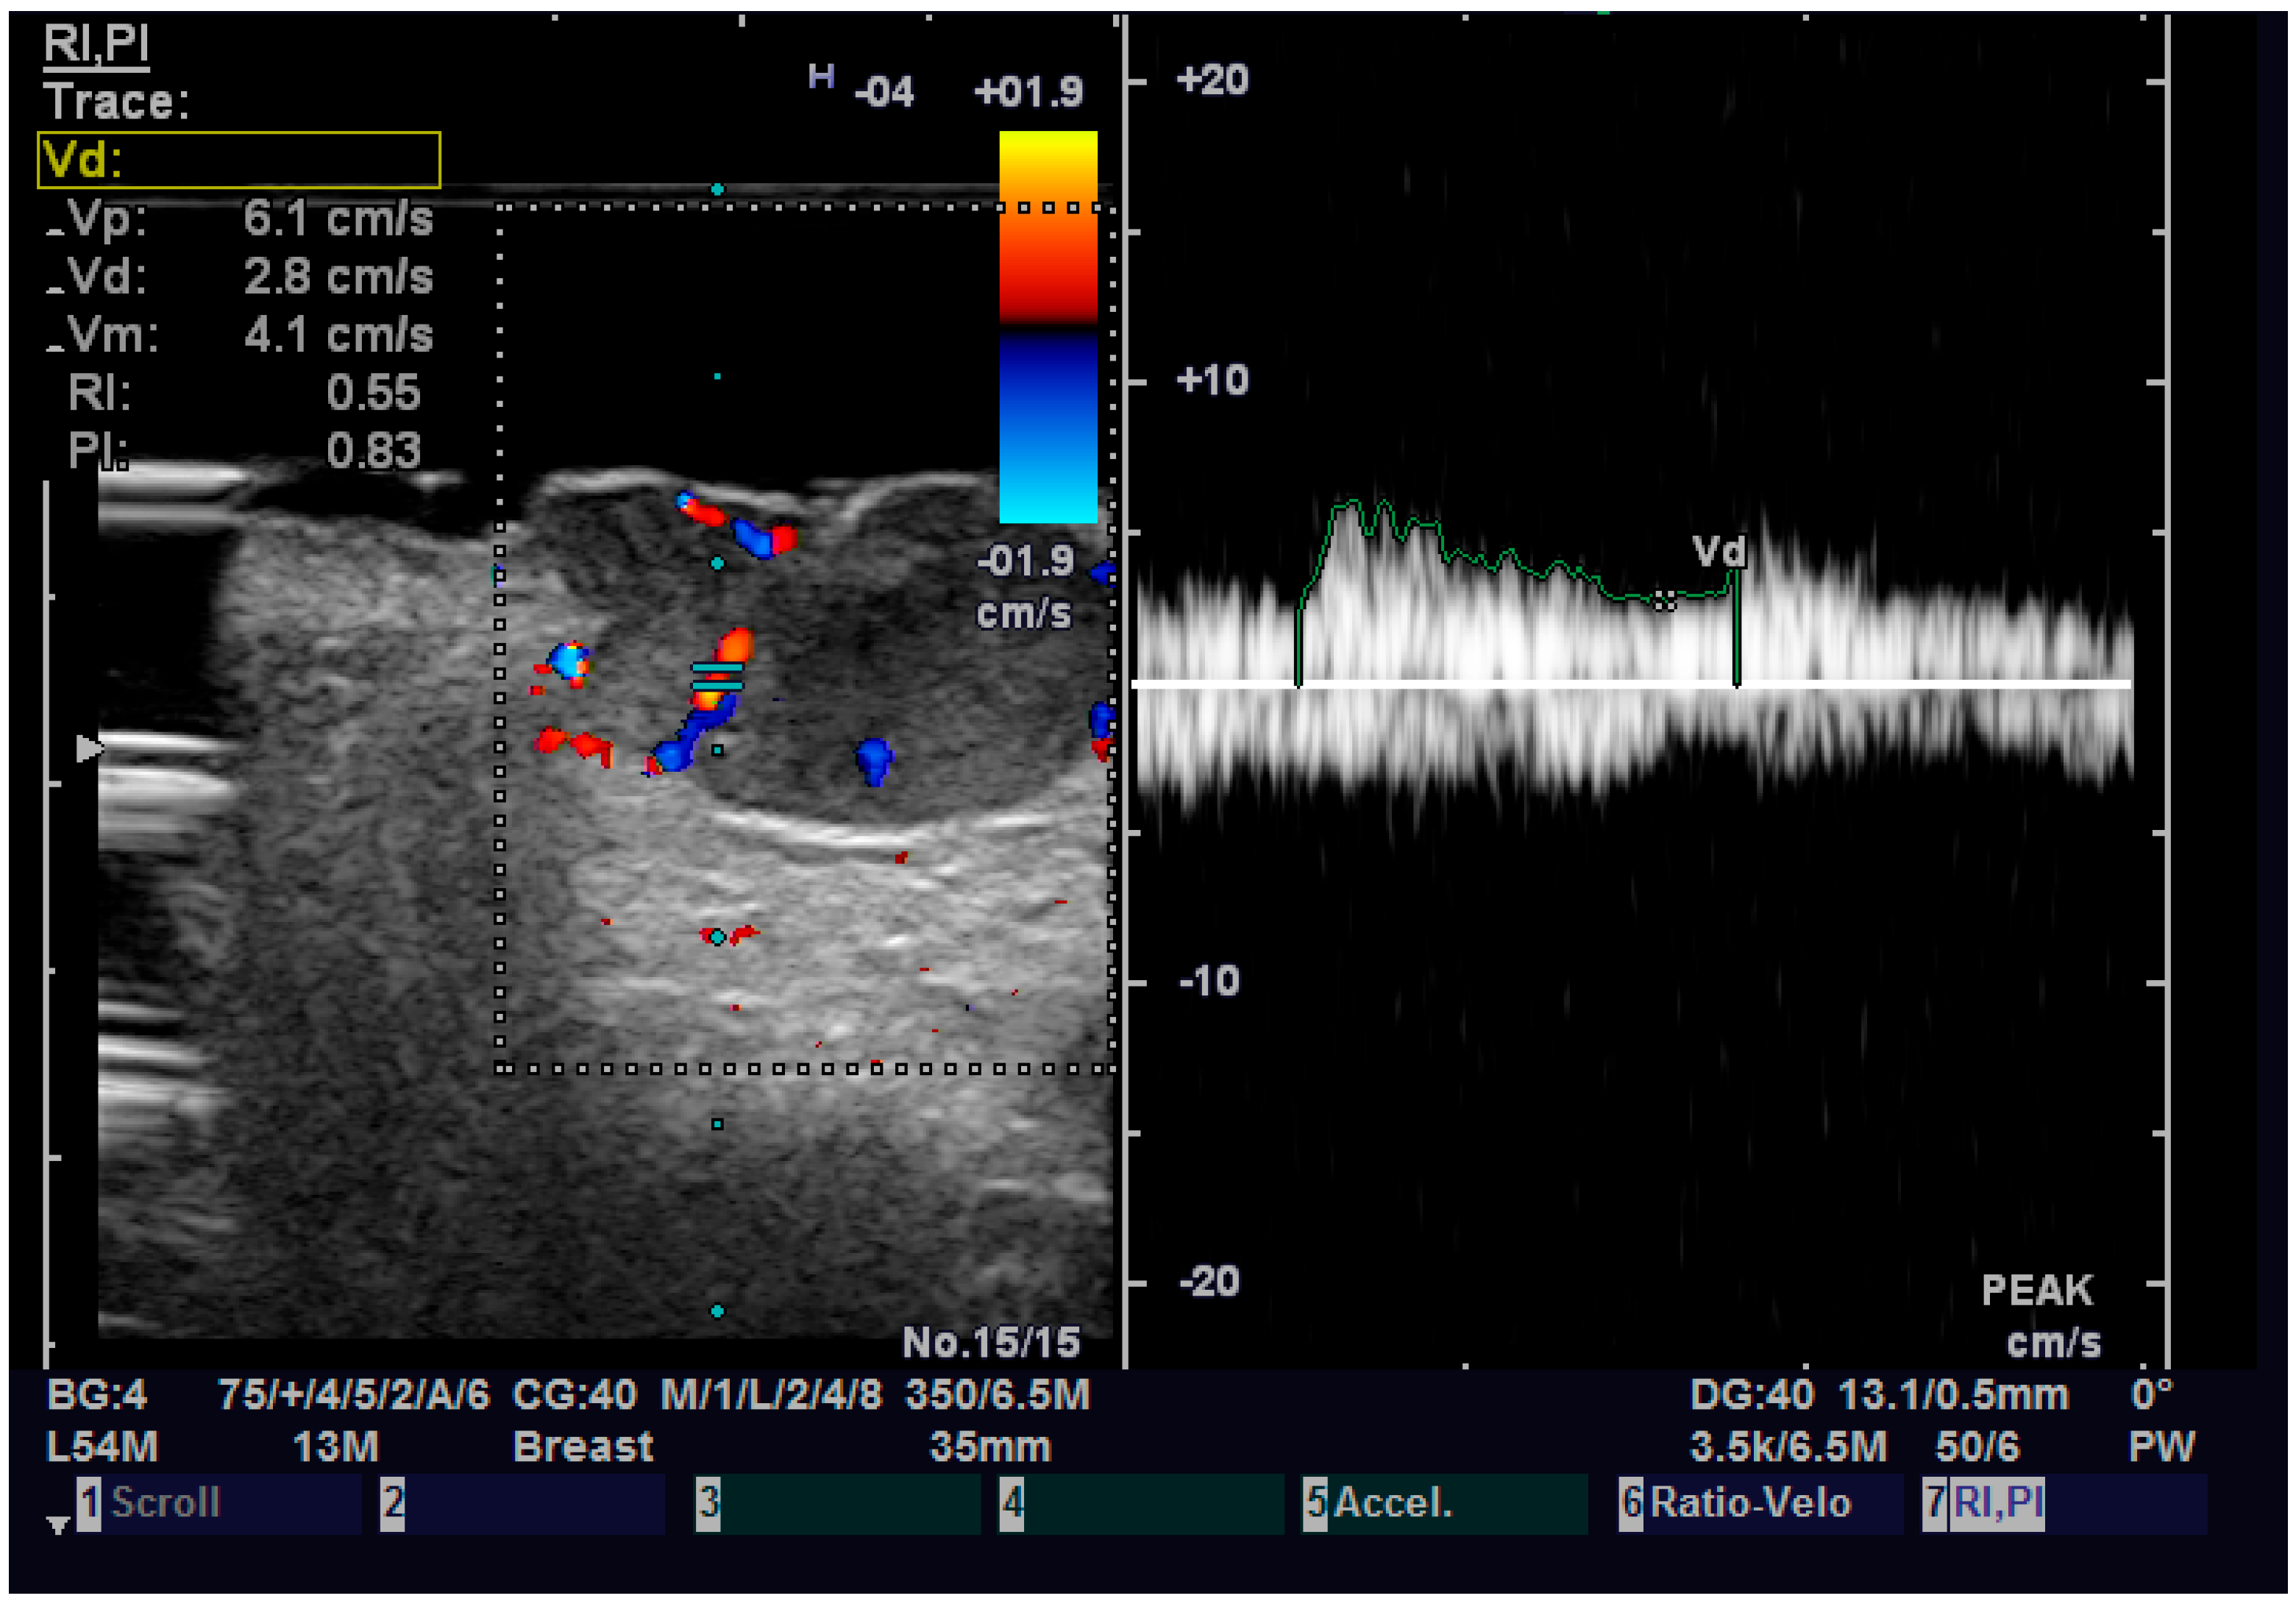

Regarding elastography, we can easily see that the tumor tissue is stiffer than the normal adjacent one (Figure 6). We did not find any significant statistical association between the value of strain ratio and the histology of the tumor. The values in the BCC group were also lower than in the SCC group (95% CI −2.98–0.35, p = 0.126). Doppler examination (Figure 7) showed increased values for both systolic and diastolic speed in the SCC group, but the results were not statistically significant and no association between the type of histology and vascularization was found (Table 4).

Figure 7.

Doppler examination of a SCC.